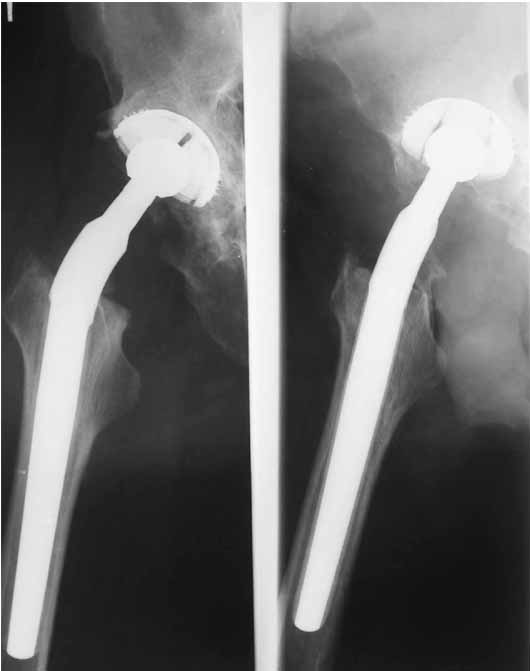

Дорогие коллеги.Мой хороший товарищ, сам травматолог-ортопед, прооперирован 1,5 мес назад. Естественно, начались проблемы. Хотелось бы узнать ваше мнениеи, главное,что делать дальше... Итак:Мужчина 50 лет.Д-з: Посттравматический деф.артроз правого тазобедренного сустава с выраженным болевым синдромом, стойкой комбинированной контрактурой иукорочением 3 см. Анамнез: 10 лет назад - сочетанная травма головы, груди, конечностей, таза... перелом заднего края вертлужной впадины и вывих бедра справа.Лечился консервативно. 25.05.94 - операция тотальное эндопротезирование правого тазобедренного сустава бесцементным эндопротезом (чашка Споторно 52, ножка Вагнера 225/21, головка L), дополнительная фиксация в кокситной гипсовой повязке в течение 3 нед. Спустя месяц после операции при поворачивании на бок в кровати произошел вывих головки эндопротеза. Под наркозом вывих вправили. Вот 10 дней лежит в постели. Что необходимо делать? Рентгенограммы до операции и после. Рентгенограммы в положении вивиха у меня отсутствуют. Ну наверное они и не столь важны, ведь вывих-то вправили. Учреждение и фамилию пациента, нашего коллеги, называть не буду. Он попросил меня собрать мнения - как ему жить дальше. Заранее благодарен. С уважением Александр Артемьев

1. Вертикальное положение чашки;

2. Нарушение угла антеверсии ножки (судя по изображению малого вертела

на послеопреационной рентгенограмме).

3. Комбинация этих двух причин.

4. Видимо, тенденция к вывиху была уже на столе - вот Вам и кокситная повязка с надеждой на фиксацию протеза рубцом.

Сан Саныч,

Консультировать вывихи по рентгенограммам, не зная хода операции, дело не очень благодарное. Я думаю, что с датой операции Вы ошиблись и это был 2004 год? Тем не менее. Настораживают два фактора. Первое - не видно большого вертела. Если с мышцами обошлись грубо и их отсекли, то это очень грустно и нужна "связанная" пара, т.н. "constrain cup". Смущает хорошо прослеживаемый малый вертел и небольшая ретроверсия чашки. Возможно это (избыточная ретроверсия ножки и чашки) могло послужить причиной вывиха. Обычно гипсовая повязка после операции не накладывается, значит, были глубокие сомнения у оперировавшего хирурга. В этом случае - ревизия с перестановкой как минимум - ножки, а как максимум - обоих компонентов.

1. AP X ray of the Pelvis is a must. It will likely show that right hip/ femur is longer than left. Even based on Rt Hip AP X Ray it is my impression.

2. 2. Acetabular component is not vertical but rather anteverted, and also small ( small size was likely used because of the deficient posterior wall of the acetabulum).

3. Femoral component is malaligned relatively to the acetabular and combination of this factors (head is also small for this patient) is the reason for dislocation.( was likely anterior)